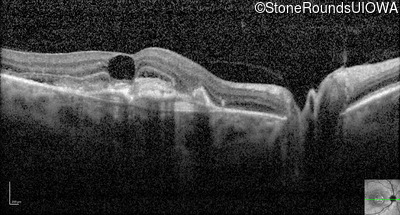

Visit at age: 59 years (Visit 2)

Optical Coherence Tomography - Right - 20/200 +1

Exemplar / OCT Stack